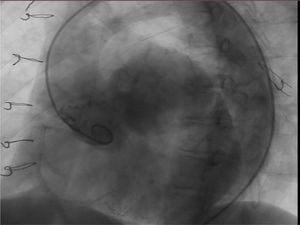

El cateterismo mostró el aneurisma con gran dilatación del seno coronario izquierdo con implante de arteria coronaria izquierda a dicho nivel del saco aneurismático. La coronaria derecha tenía características normales. Se objetiva insuficiencia valvular leve (fig. 4).